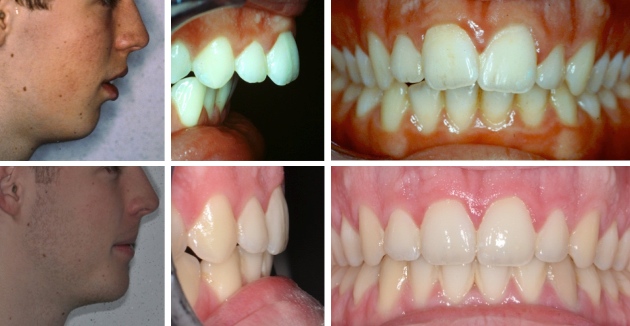

Fall 1: Vergrösserter Überbiss durch Unterkieferrücklage

Therapie: Nachtspange und festsitzende Spange